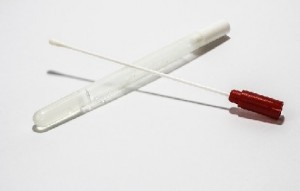

- Test de detección rápida de antígeno estreptocócico en exudado amigdalar: Es una prueba sencilla. Con un isopo se recoge saliva de las amígdalas y faríngea. Se le aplican una serie de reactivos a la muestra, que luego se testea para obtener un resultado en pocos minutos. Cuando es positivo indica que la causa es la bacteria Streptococcus pyogenes, muy típica causante de anginas.

- Cultivo faríngeo: de nuevo con un isopo se recoge muestra amigdalar y faríngea para esta vez ser cultivada en laboratorio y determinar el germen que ocasiona la sintomatología. Tiene el inconveniente en que tarda varios días en conocerse el resultado, por lo que hay que empezar el tratamiento antes de saber qué germen lo ocasiona.